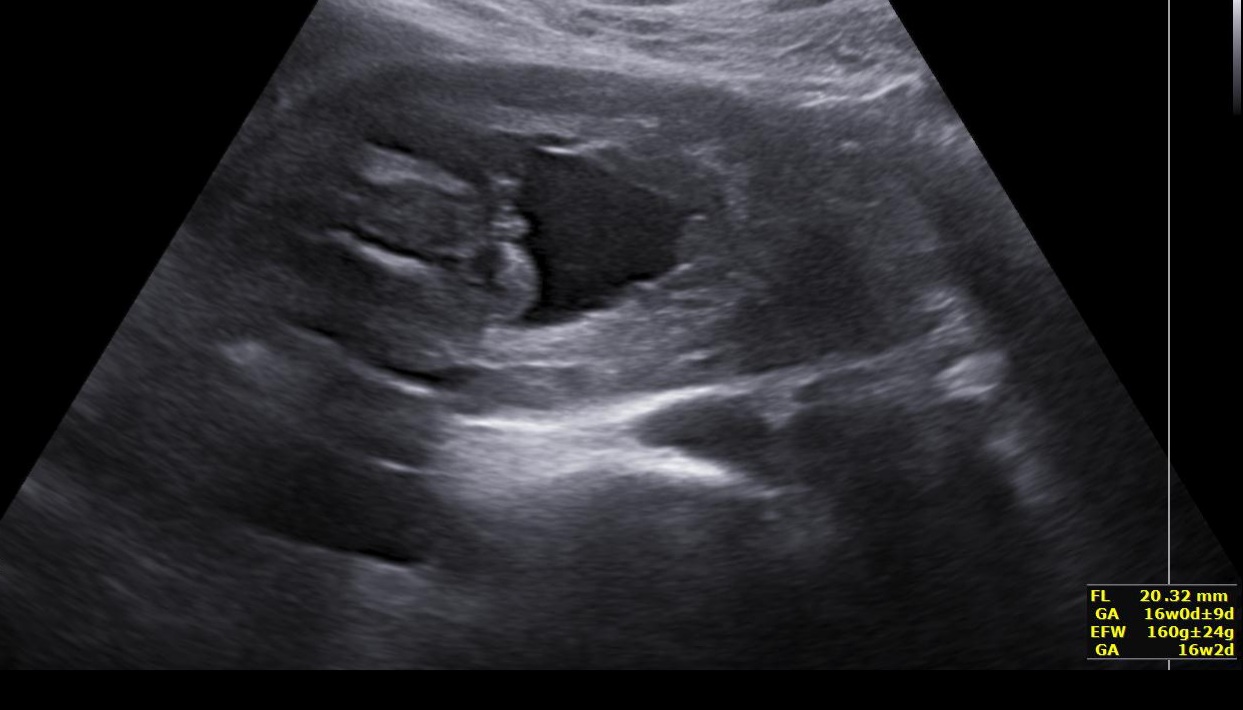

Pohlaví dle ultrazvuku mezi nožičkami. Pozná Vaše zkušenějši oko?

dnes jsem byla na těhotenské kontrole (16+5) a kontrolu prováděla asistentka, která zatím není tolik zkušená a netroufla si určit pohlaví dle utz.

Chtěla bych se zeptat, zda Vaše zkušenější oko ze snímku náhodou pohlaví nepozná?

z tohoto snímku si hádat netroufnu. Ono, málokdy je snímek z tak přesné roviny a dostatečné kvality, aby se k tomu šlo vyjádřit. Snímek nedokáže nikdy nahradit vyšetření v reálném čase. Takže vyčkejte do 20. týdne na další ultrazvukové vyšetření. 🙂